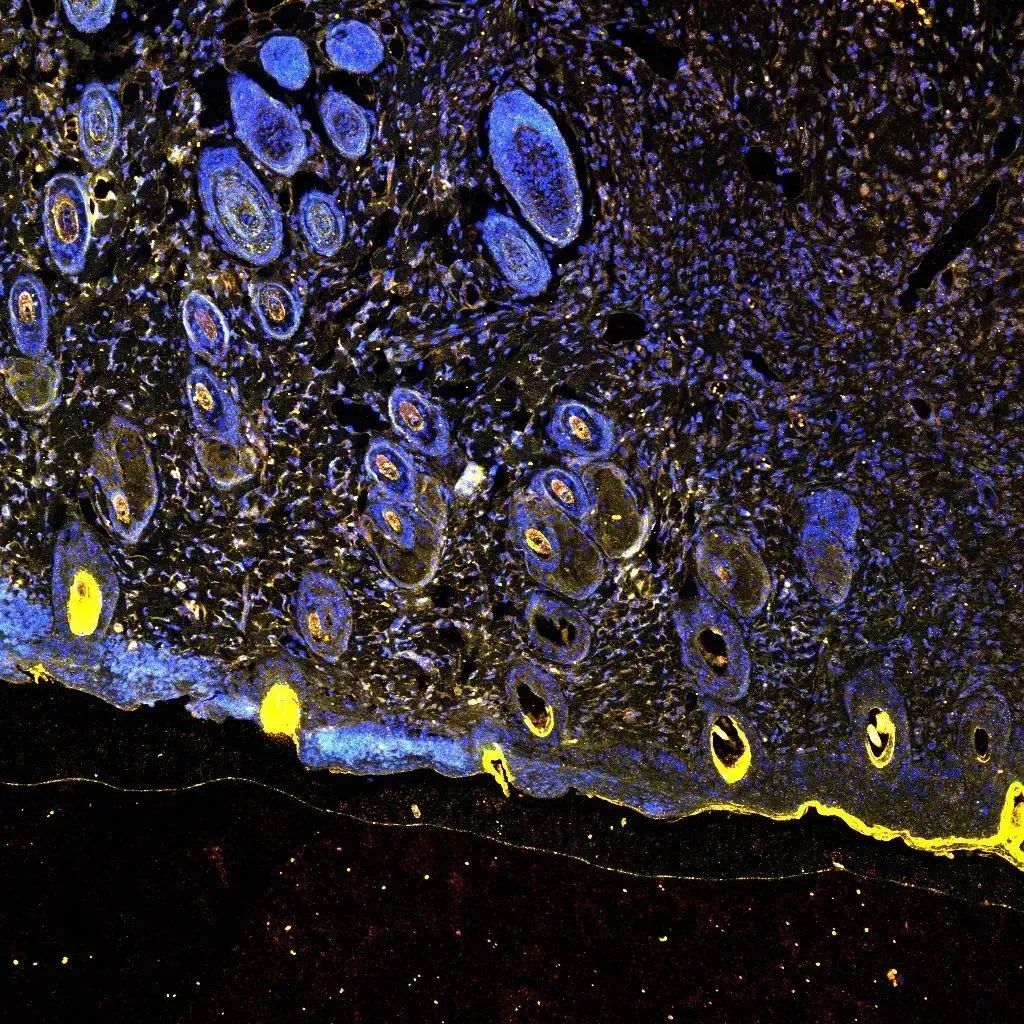

《星空之巢》

刘秋贝 (基础医学与法医学院 2022级基础医学专业研究生)

小鼠睾丸切片的免疫荧光染色,相应蛋白染料和DAPI染色后的merge图像,图中一个个的圆形小管为小鼠睾丸内生精小管。从微观到宏观,从简单到复杂,科学的探索永无止境,共同谱写生命的壮丽诗篇。